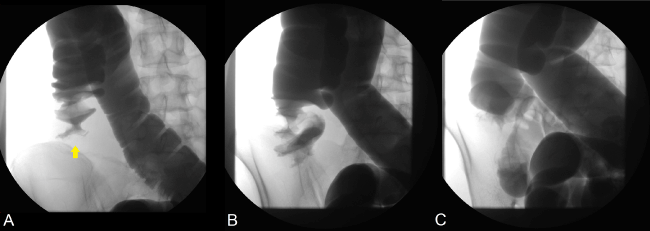

Laboratory findings on admission revealed only mild leukocytosis (9,520 /μL) and no other abnormalities. Abdominal ultrasound showed a mass forming a “donut sign” in the right lower quadrant (Figure 1, arrow). Computed tomography scan also confirmed a “target mass” consisting of two superimposed concentric radiolucent circles in the ileocolic region (Figure 2, arrow). A diagnosis of ileocolic intussusception was made and non-operative reduction using contrast enema was performed under fluoroscopic guidance (Figure 3).

During reduction, examination with contrast enema revealed a filling defect, also known as a “cup-shaped filling” or “claw-like appearance”, within the lumen of the proximal portion of the ascending colon which confirms the diagnosis of ileocolic intussusception (Figure 3A, arrow). Reduction using hydrostatic pressure was successful as indicated by the free flow of contrast agent into the distal ileum (Figures 3B and 3C). After reduction, her symptoms improved remarkably and on day 2 after admission, total colonoscopy was performed to check for any lesions that may serve as possible lead points. Although moderate to severe mucosal edema as well as erythema with mild erosions were observed in the cecum and ileocecal valve, there were no lesions (including in the terminal ileum) that could specifically be identified as lead points for intussusception (Figure 4). Biopsy demonstrated inflammatory change that was compatible with ischemic colitis. We regarded these endoscopic findings as ischemic changes secondary to intussusception rather than the cause of it.

Figure 3. Fluoroscopic imaging of non-operative reduction using hydrostatic pressure from contrast enema.